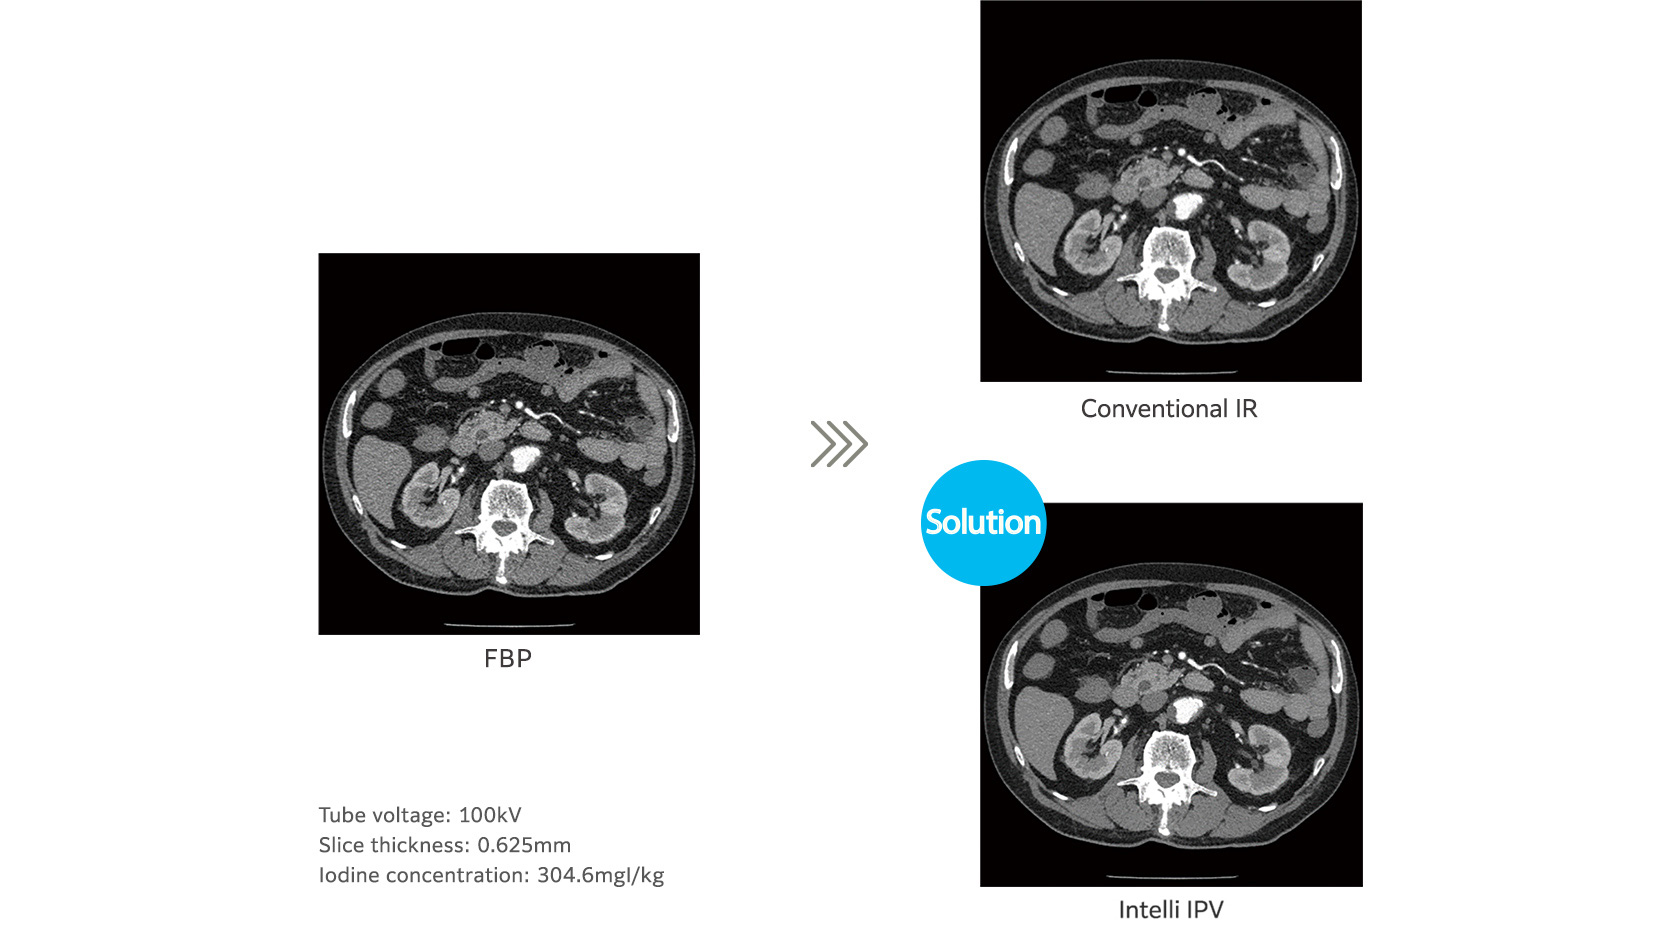

Iterative processing Intelli IPV maintains normal image texture, even at a high dose reduction ratio, as well as reducing the noise, resulting in improved visibility. Vision Model Technology makes this possible. The technology controls image noise and quality by iterative arithmetic processing based on a statistical model, an object model and a physics model.

Intelli IPV achieves an image texture similar to FBP images by making the NPS (noise power spectrum) close to that of the FBP, as well as improving the low contrast detectability by up to 2 times.

Achieves image noise reduction up to 90%, radiation dose reduction up to 83%, and improves low contrast detection capability up to 2 times.